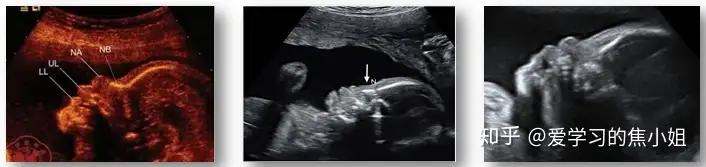

三、鼻骨缺失

鼻骨是胎儿鼻梁内的薄回声带。胎儿面部面对探头,成像面在颜面部正中矢状切面,超声声束与鼻骨长轴成90°,测量两端鼻骨边界的距离。

鼻骨短小:其长度小于同孕周正常值的第2.5百分位数。

十、单脐动脉

单脐动脉(SUA):在胎儿脐索内及膀胱周围仅有一条脐动脉,另一条脐动脉缺如。单纯单脐动脉与胎儿单倍体畸形无关,与胎儿非染色体异常的关系: 与胎儿肾脏发育不良、心脏畸形和低体重儿有关。发现胎儿有单脐动脉时,应仔细检查其他解剖结构,超声评估并随访观察胎儿生长发育情况。合并畸形或见染色体异常软指标,应做胎儿染色体检查。

SUA可以单发,合并染色体异常及其他畸形也不少见,约50%的18三体和 10%-50%13三体儿伴有SUA。最近有报道SUA发生心脏畸形、肾脏畸形和IUGR(宫内生长受限)的风险明显增加。